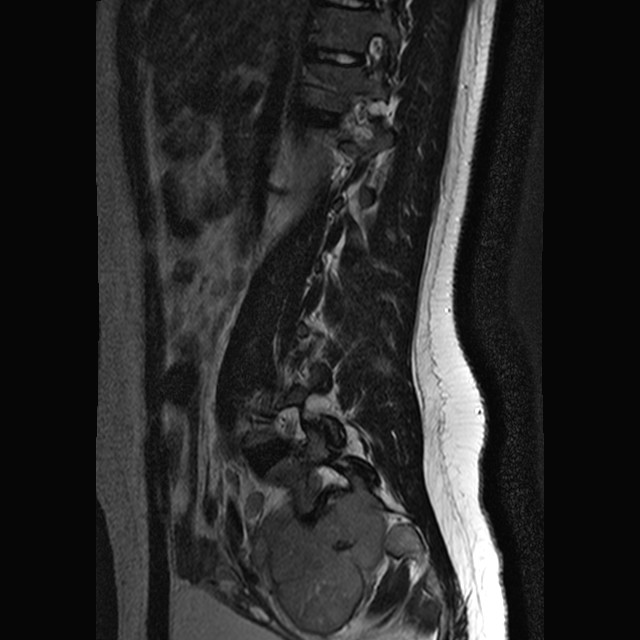

1.    The patient was a 3 year-old girl with the chief complain of left lower extremity that extended to the right side. Imaging demonstrated a large sacral mass that mainly affects her left side. These features are not sufficient for a definitive diagnosis but which of the following be the most likely diagnosis?  Answer

CT taken at the time

of the needle biopsy

(needle is shown here)

MRI FNA